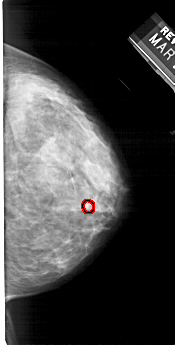

FILE: A_1256_1.RIGHT_CC.OVERLAY

TOTAL_ABNORMALITIES 1

ABNORMALITY 1

LESION_TYPE CALCIFICATION TYPE PLEOMORPHIC DISTRIBUTION CLUSTERED

ASSESSMENT 4

SUBTLETY 3

PATHOLOGY MALIGNANT

TOTAL_OUTLINES 1

BOUNDARY